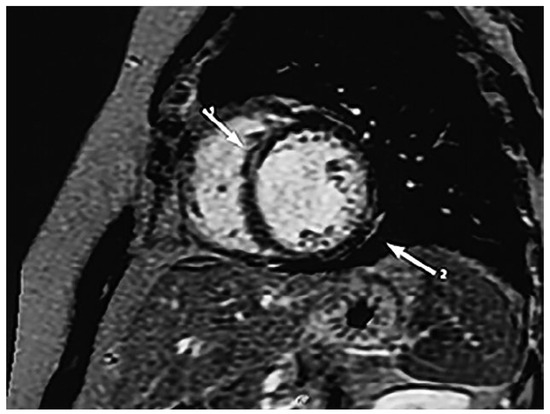

Chagas heart disease is becoming a worldwide health burden and represents a major cause of cardiovascular death in areas where it is endemic. Although rarely observed in Switzerland, increased awareness of the disease is important, particularly in times of global migration and mobility. Chagas disease is caused by Trypanosoma cruzi, which is transmitted by infected triotamine bugs. The spectrum of cardiac involvement is variable. It ranges from an acute cardiac infection to chronic myocardial fibrosis. Acute infection is often asymptomatic and resolves spontaneously in up to 90% of cases, but it may also lead to an indeterminate form of chronic Chagas disease with positivity for antibodies against T. cruzi. Thirty to forty percent of patients with indeterminate Chagas disease have involvement of the heart (Chagas cardiomyopathy), oesophagus (megaoesophagus), colon (megacolon), or all of these organs. The chronic disease is diagnosed by compatible clinical presentation (cardiac, digestive or cardio-digestive), and detection of antibodies against T. cruzi antigens at least in two different serological tests. The acute disease is treated with benznidazole or nifurtimox, which are strongly recommended for all cases of acute, congenital or reactivated infection, including in children. Drug treatment can be offered to adults up to 50 years of age without advanced Chagas heart disease. During pregnancy, in severe hepatic or renal insufficiency and in advanced Chagas heart disease, treatment is not recommended. The treatment options of these patients are limited to heart failure medication. The present article presents a patient with newly diagnosed Chagas cardiomyopathy, who was admitted to our hospital with symptoms of heart failure. We provide an overview of Chagas disease in the current literature. Full article

Show Figures

Figure 1